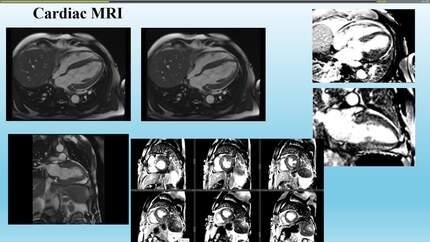

From storage to ischemia and inflammation: the progressive journey of late-diagnosed fabry cardiomyopathy